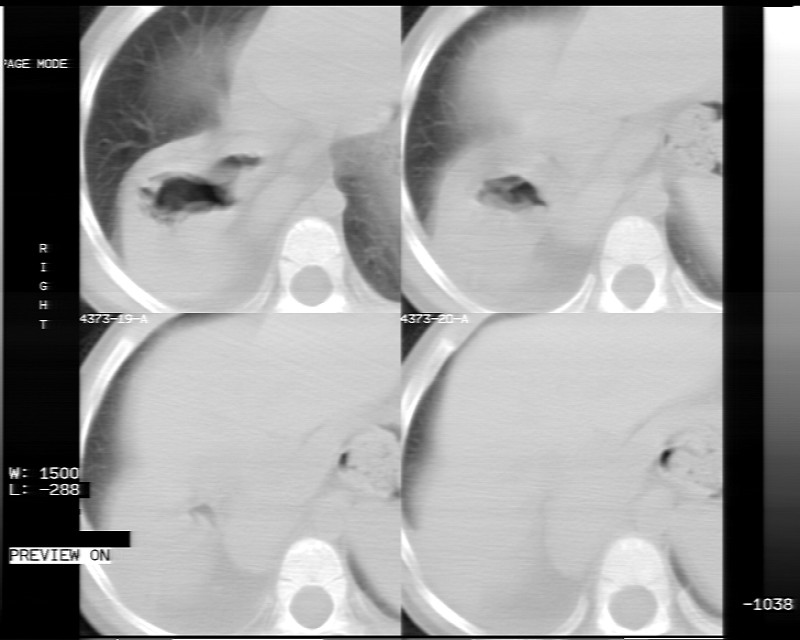

男性,3岁,斜疝术前常规检查胸片体检发现右下肺病变。咳嗽,无发烧。

内有气体,液平面,考虑食管裂孔疝可能性大。建议食道钡透。

有液气平面,前部肺纹理聚集(受压改变),周围肺野及相邻胸膜清晰,支持膈疝,可吞服造影剂看一下。

考虑膈疝(右侧胸腹膜裂孔疝?)。